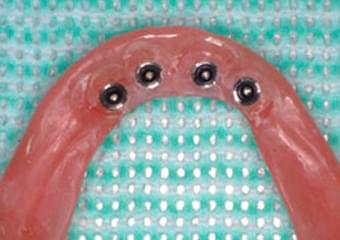

義歯の維持装置